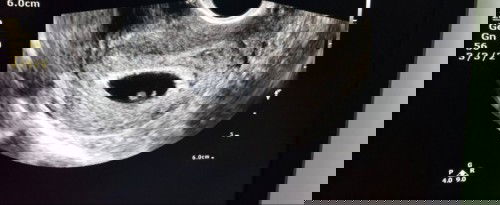

ท้องสอง8W พบภาวะแท้งคุกคามแม่มีตกขาวสีน้ำตาลออกกระปริบกระปอย แบบนี้น้องจะปลอดภัยไหม

สอบถามแม่ๆในนี้หน่อยค่ะใครเคยพบปัญหาภาวะแท้งคุกคามแบบนี้บ้างคะ น้องจะปลอดภัยดีไหม แม่มีโอกาสจะได้ตั้งครรภ์ต่อไปไหม หลังจากมีอาการตกขาวสีน้ำตาลได้สามวันแม่ไปหาหมอซาวน์ล่าสุดยังพบตัวอ่อนของน้องและเสียงหัวใจเต้น หมอให้หยุดพักนอนนิ่งๆ1สัปดาห์ แต่ตกขาวสีน้ำตาลก็ยังออกมาอยู่เรื่อยๆ แม่แอบห่วงน้อง และเป็นกังวลมากค่ะ #ขอคำแนะนำหน่อยค่ะ #คุณแม่ๆช่วยแนะนำหน่อยค่ะ #ขอบคุณสำหรับคำตอบค่ะ